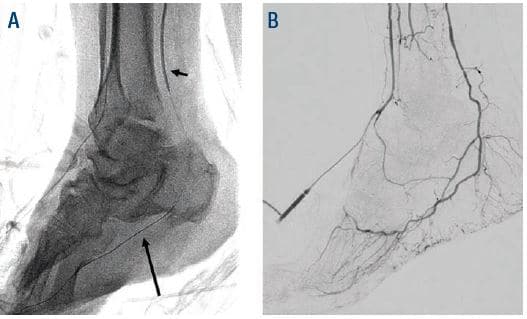

Anticipating a high risk of complications related to transfemoral access, we decided to proceed with TAMI approach with transradial guidance. A 4- to 5-Fr Glidesheath Slender (GSS) (Terumo Medical) was inserted in the right radial artery for visualization of the proximal vessels. We placed a 2.9-Fr Cook pedal (Cook Medical) sheath in the ATA and advanced a 0.018-inch CXI (Cook Medical) support catheter over a 0.018-inch Command ST (Abbott Vascular) wire. The CXI catheter and wire were advanced through the course of the ATA intraluminally except for the ostium of the ATA where the wire entered a subintimal space. Thereafter, we gained access in the right PT with a 4- to 5-Fr GSS sheath to serve as an antegrade access to cross the ATA CTO (Figure 2). A 0.018-inch CXI support catheter was telescoped within a 4-Fr Berenstein (Boston Scientific) catheter with a 0.018-inch Command wire advanced into the proximal ATA (Figure 3). The antegrade equipment was advanced into the distal ATA. The retrograde CXI catheter was pulled back in the distal AT where the antegrade wire was inserted for externalization. Subsequently the antegrade CXI catheter was externalized through the retrograde 2.9-Fr sheath placed in the distal ATA (Figure 4). The 0.018-inch Command wire was exchanged for a 0.014-inch ViperWire (Cardiovascular Systems, Inc.) guidewire to perform therectomy using a 1.5 mm Classic CSI Diamondback 360 catheter in the PTA, TPT, and ATA (Figure 5). Thereafter, based on extra vascular ultrasound (EVUS) measurements, we performed balloon angioplasty of proximal DPA, ATA, and PTA with a 3.5-x 300-mm balloon (Ultraverse BD Bard), and TPT with a 4.0- x 60-mm Lutonix DCB (BD Bard) with an excellent result (Figure 6).

A 3.0- x 80-mm Advance Micro 14 2.5-Fr (Cook Medical) balloon was inserted through the retrograde ATA 2.9-Fr sheath over the ViperWire guidewire which was exchanged for a 0.014-inch Fielder XT (Asahi Intecc) and advanced distally to the 4- to 5-Fr GSS PTA access for intraarterial balloon tamponade to obtain hemostasis (Figure 7). Finally, the retrograde 2.9 Fr ATA sheath was removed, and hemostasis was achieved with manual pressure (Figure 8). He tolerated the procedure well and ambulated an hour later. He underwent additional debridement and placement of a wound vac.